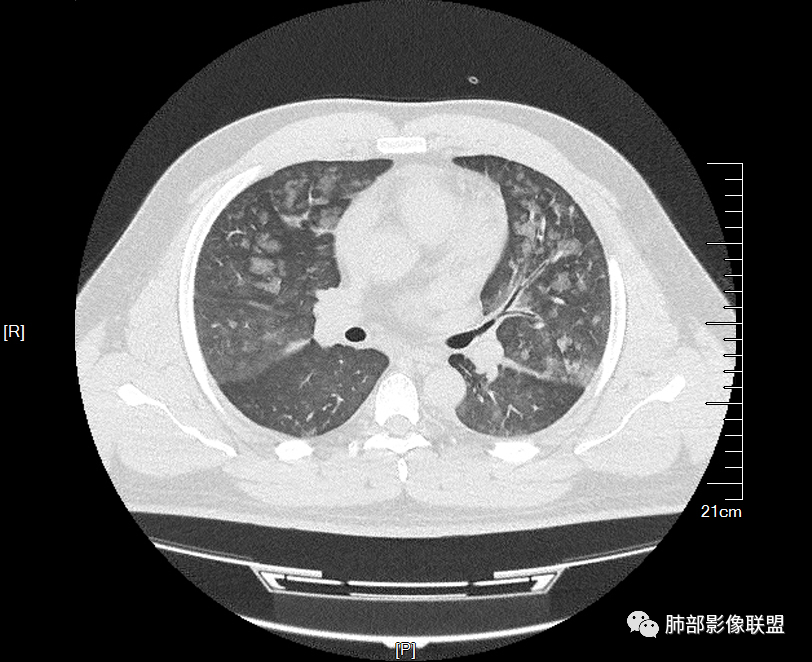

年轻男性,痛风史,高血压史,肌酐高,左足痛6天入院。胸CT:双肺多发弥漫性磨玻璃结节影,大小不一,部分融合,上中下肺都有,中内带多,胸膜下少。部分血管束略增粗,小叶内间隔、小叶间隔增厚,下肺明显,左室大。叶裂胸膜增厚。临床有痛风,左足痛6天,考虑:心衰、间质性肺水肿?弥漫性肺泡出血?鉴别:MPA,肺肾综合征,痛风结节等。

青年男性,有肾功能不全史和痛风史,这个影像分布有个典型的特点,全部是以中央间质周围的渗出性改变,这个改变主要就是两种可能,一种是肾功能不全导致的血管通透性增高导致的肾性肺水肿,一种是出血导致的DAH改变,具体是哪种,影像上不好简单的鉴别,需要结合更多临床资料综合分析。

年轻男性,痛风,肌酐高,提示肾功能有损,两肺多发磨玻璃腺泡结节,小叶间隔增厚,双侧少许胸水,血管增粗,考虑肾性肺水肿,DAD,鉴别肺肾综合征,需要更多临床资料

小叶间隔增厚,无明显重力趋势

少量积液,脂肪肝

这里有一点重力趋势

中轴间质稍增厚

细网格也明显

中轴间质增厚,小叶间隔增厚,小叶内间质增厚,部分重力作用,双侧对称,胸水,按理淋巴道回流受阻有

肺水肿类病变有

问题是腺泡结节如何解释?

病例结果:肺水肿

肺水肿肯定有

但是单纯性肺水肿不好解释

肾性肺水肿症状可以不明显,尤其是这个病人已经有小叶间隔增厚,说明病程比较长,耐受较好了

1.间质性肺水肿 :小叶间隔增厚,尚光滑,支气管血管束增粗,胸膜或叶间裂增厚,肺内有磨玻璃密度影,有重力分布趋势。

2.肺泡性肺水肿 :

(1)中央型分布:以肺门为中心,两肺中内带对称分布的大片状实变,称为“蝶翼征”。常见于心源性及肾源性肺水肿患者。也可表现为磨玻璃密度病灶,弥漫性分布或以小叶中心性分布。

(2)弥漫型肺水肿:弥漫分布于两肺内的多发斑片状磨玻璃密度及实变影,大小和密度不等,可融合成大片状阴影,可见空气支气管征。